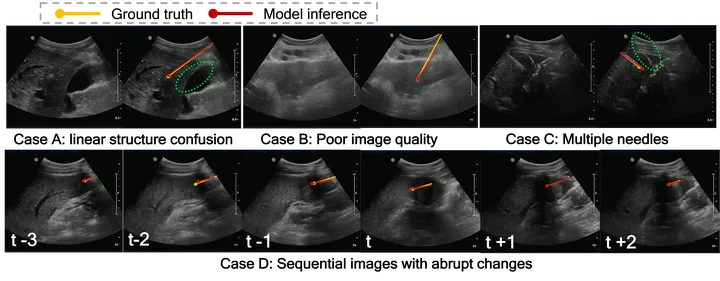

Objective: In US-guided percutaneous thermal ablation, to eradicate the entire cancerous cells, accurately inserting the needle (i.e., ablation applicator) into the tumour as planned is a crucial step during real-time US guidance. However, due to complex US artifacts and image contrast between the needle and adjacent tissues, identifying the needle, particularly the needle tip, has been considered as a difficult problem. Therefore, our work aims to develop a deep learning-based approach using acquired sequential US frames for real-time needle identification.

[1] Deep learning-based Needle Tracking in US-guided Percutaneous Liver Tumor Ablations. (see detail)